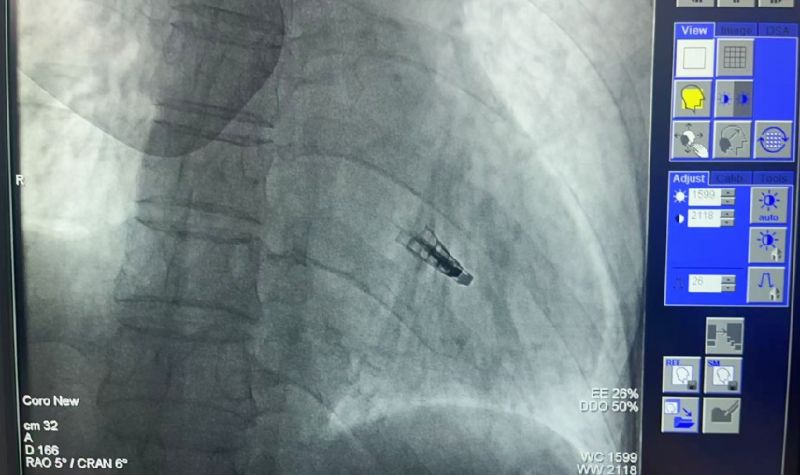

2025年5月9日,延安大學咸陽醫(yī)院常務副院長兼心血管病院院長吳棟梁介入團隊成功為一名73歲“二尖瓣大量返流”患者實施咸陽市首例《經(jīng)導管二尖瓣緣對緣修復術(shù)(TEER)》。

創(chuàng)傷極小:不開胸的“心臟修補術(shù)”。僅通過股靜脈穿刺,經(jīng)導管送入夾合器精準修復二尖瓣,避免傳統(tǒng)開胸、體外循環(huán)等高風險操作。

高效精準:手術(shù)耗時僅1-2小時,術(shù)后患者即刻返流顯著減少,血流動力學明顯改善。

術(shù)前吳棟梁院長、劉雄濤院長、張樹遠責任總醫(yī)師再次深入的評估患者整體病情及手術(shù)指征,于2025年5月9日下午成功為患者實施了TEER技術(shù),解除了其病痛,術(shù)后第一天患者即表示“呼吸順暢了,整個人都輕松了”。